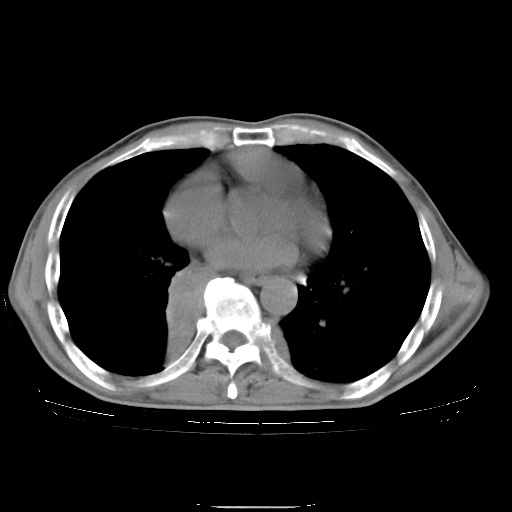

男性患者,63岁。右侧胸背部疼痛2月,加重一周。

考虑:右肺中央型肺癌并右肺下叶不张;两肺尖继发性肺结核。

右下中央型肺癌伴肺内纵膈转移。

右下肺中心型肺癌并肺不张

纵隔淋巴结转移

考虑右中心型肺癌并右下肺不张,肺及纵隔,左肋骨转移。

右肺下叶支气管狭窄闭塞,右下肺不张,气管前间隙淋巴结肿大,两上肺散在分部粟粒灶,沿肺血管支气管束分部,血管支气管束走形较为光滑。考虑右肺中心型肺癌合并肺不张,纵隔淋巴结转移,两上肺癌性淋巴管炎